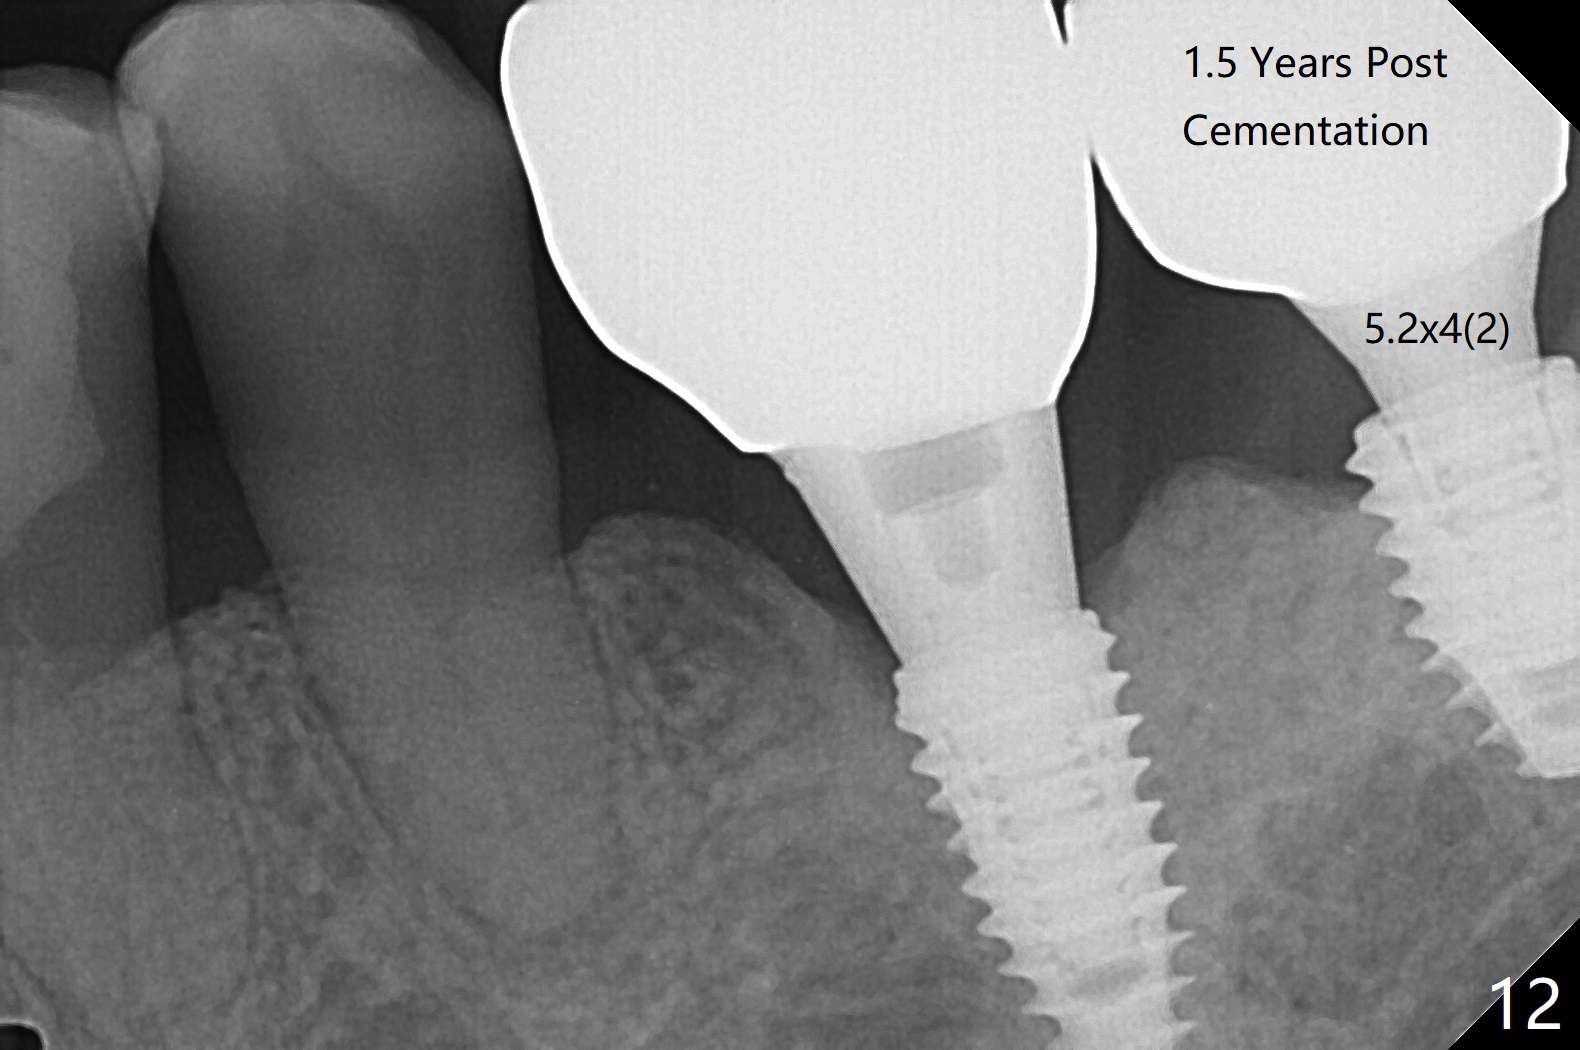

The implants at #12 and 14 are placed 1 month later (Fig.4). The 4 implants have impression (Fig.5,6) and cementation (Fig.7-9) at the same time. Although the upper FPD is able to be removed after cementation in the mouth (Fig.7), the abutment screw cannot be tightened >20 Ncm (Fig.8). The tooth #15 is tender early after crown/FPD cementation and needs occlusal adjustment twice. The crown of #18 dislodges eight months post cementation (Fig.11 taken after recementation). There is no bone loss at #13 and 15 (Fig.10), while the bone density increases around the implants at #18 and 19 eight months post cementation (Fig.11). The abutment screw at #18 become loose 1.5 years post cementation; after proximal surface trimming twice (<), the abutment remains incompletely seated (Fig.12,13). With suspicion of soft tissue block (Fig.13 *), a small abutment with longer cuff is completely seated (Fig.14).